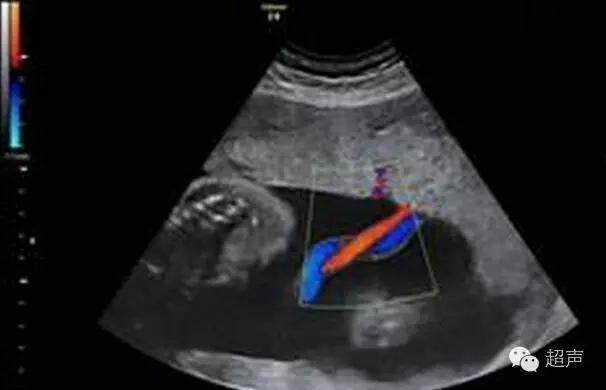

當醫生繼續在我肚皮上照超聲波,不斷細心地告訴我這是5隻手指、5隻腳指、眼窩好深,他日必定大眼妹。突然他面有點難色告訴我們:「你們看看這裡(浮標指著一藍色一紅色位置),他告訴我們:『正常嬰兒臍帶是由兩條臍動脈與一條臍靜脈所組成,但你女兒有點特別,她只有一條臍動脈及臍靜脈』,我立刻問醫生:『有什麼問題(當時腦海中立即想到一生的缺憾或者害了她的事,在超聲波床上流了眼淚)醫生向我們解釋是基因的問題,不是你或先生控制到的問題。在我醫生生涯中都曾經見過,比例大概200個準媽媽都有一個會有這種情況,有部份嬰兒出生後會有心臟問題、腎的問題。但唔係所有單臍帶動脈的BB都有呢類病,又會有啲BB會比較輕磅、瘦,更嚴重既可能會出生後靠機器維生,所以我而家會寫紙俾你排期去公立跟進。」晴天霹靂的感覺絕對能夠充分應用在我身上。

這圖只有一紅一藍,正常的BB有兩紅一藍